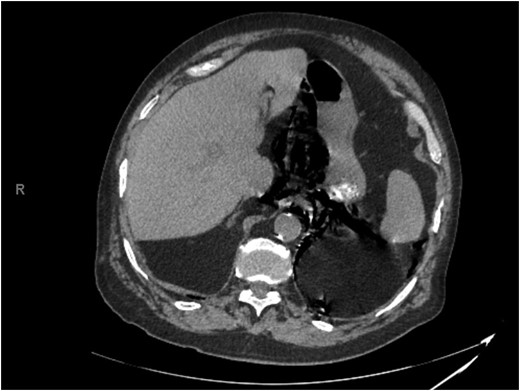

Abdominal CT showed pneumomediastinum and pneumoperitoneum secondary to perforated hollow viscus necessitating emergent exploratory laparotomy (Figs 1 and 2). Lysis of adhesions, right hemicolectomy with primary ileocolic anastomosis, and umbilical hernia repair were performed. NGT placement after induction of general anesthesia was noted to be difficult secondary to resistance met with advancement of the catheter. Postoperatively, the patient was transferred to the surgical intensive care unit (SICU) in stable condition.

Representative slice from abdominal computed tomography imaging on admission.